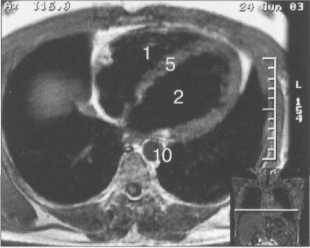

Рис. 9.47. МРТ сердца. Аксиальная плоскость.

Здесь и на рис. 9.48—9.52:

I — правый желудочек, 2 — левый желудочек, 3 — правое предсердие, 4 — левое предсердие, 5 — межжелудочковая перегородка, 6 — межпредсердная перегородка, 7 — задняя стенка левого желудочка, 8 — восходящая часть аорты, 9 — дуга аорты, 10 — нисходящая часть аорты, 11 — легочный ствол, 12 — правая легочная артерия. 13 — левая легочная артерия, 14 — верхняя полая вена, 15 — нижняя полая вена, 16 — трахея.

На рис. 9.47—9.52 представлены Т1-ВИ наиболее часто используемых МР-сечений сердца.